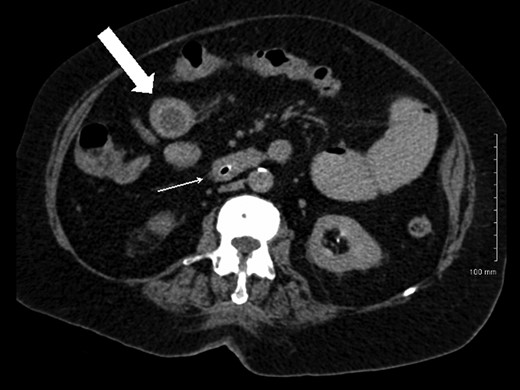

A plain abdominal radiograph was also unrevealing. She proceeded to have computerized tomography (CT) scan of her abdomen and pelvis, which showed dilated small bowel loops consistent with small bowel obstruction. There were two filling defects noted, one in her proximal ileum suspicious for a non-calcified gallstone and the second distally in her terminal ileum (Figs 1 and 2). Appearances were suggestive of gallstone ileus. She was adequately resuscitated and underwent a laparotomy. The small bowel was narrowed in two segments: proximally secondary to an impacted gallstone and an area of stricturing noted distally. Both segments were resected with end-to-end anastomosis performed in a two-layer standard hand-sewn fashion. The clinical impression was one of dual pathology including Crohn's disease and gallstone ileus. She did not undergo a cholecystectomy or repair of her cholecystoduodenal fistula. She made an uneventful post-operative recovery and was discharged home well on Day 7.

Axial CT image demonstrating gallstone in proximal ileum (block arrow) and distal ileal luminal narrowing (thin arrow).